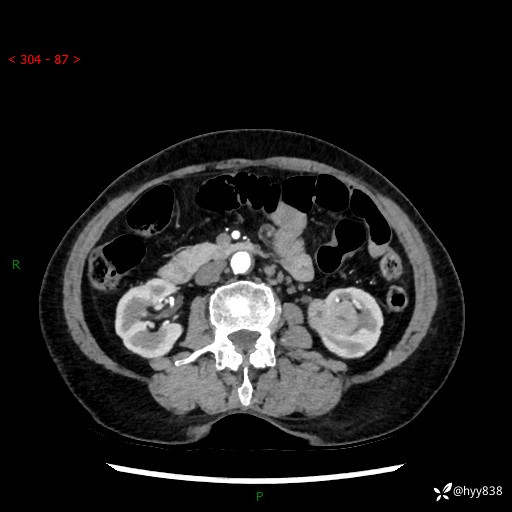

72岁/女,检查发现左肾占位1天。为了满足诊断,常规四期后,又加了延迟期-结果公布~

【患者信息】:72岁/女

【主诉】:检查发现左肾占位1天

【现病史及既往史】:患者于1天前检查发现左肾占位,无畏寒发热,无咳嗽咳痰,无腰腹部疼痛不适,无肉眼血尿、无尿频尿急症状,起病来,患者未行特殊治疗,为求进一步诊治,门诊以"左肾占位"收治入院。 发病来患者精神、饮食、睡眠良好,小便如上,大便正常,体重无明显变化。

【检查】:肾脏CT平扫+增强